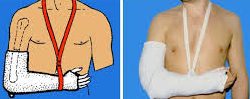

- Les fractures peu ou non déplacées peuvent être traitées par une immobilisation, néanmoins cette immobilisation est longue, et peut se révéler inconfortable, et enraidissante pour le coude.

La durée d’immobilisation dépend du traitement choisi : en moyenne de 3-4 semaines